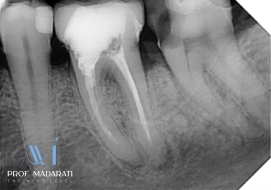

Chief Complaint & Diagnosis: Irreversible pulpitis in tooth #37 (mandibular left second molar).

Pre-operative Assessment: Radiographic examination revealed S-shaped, severely curved, and calcified (obliterated) mesial canals, presenting a high-complexity anatomical challenge.